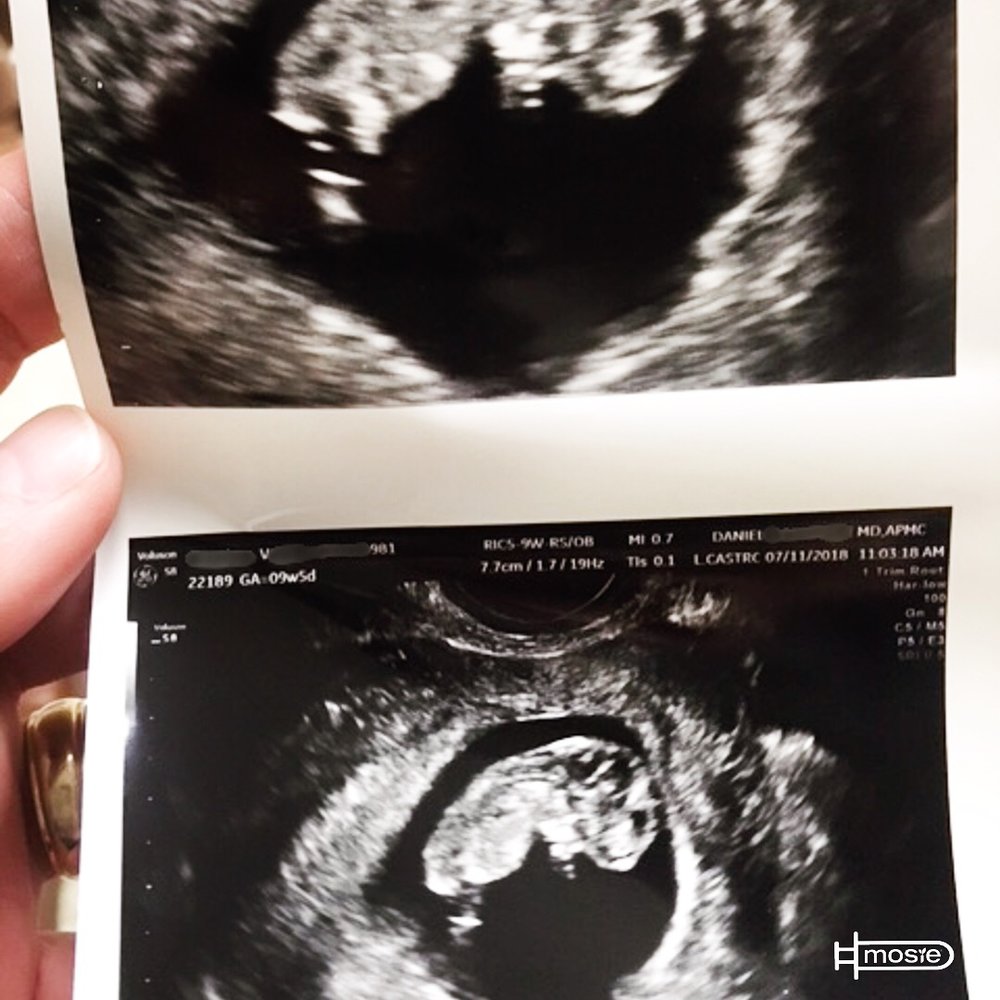

We did it! The first time we attempted Mosie we were pregnant. We were one appointment away from starting IVF treatment. We had been trying for 2 years with no success. Below is a photo from todays 9 1/2 week ultrasound. We are told we have a healthy baby with a very strong heartbeat. We are beyond excited and so grateful for Mosie!